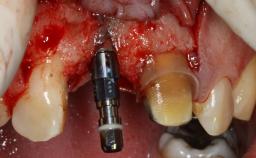

Replacement of Multiple Teeth in a Partially Dentate Posterior Mandible with a Fixed Dental Prosthesis Using a Flapless Approach

An 80-year-old female patient was referred to clinic for rehabilitation of her dentition. The patient’s medical history revealed no significant findings that would preclude routine dental and oral surgical procedures. She reported no drug allergies and was currently taking no prescription medications.

Her chief complaint was her inability to masticate efficiently due to the recent loss of her mandibular second premolars and first molars bilaterally. She expressed a desire for fixed prostheses in the shortest possible time due to her advanced age, requesting that replacement teeth should look as natural as possible. She was otherwise comfortable and not experiencing any symptoms from her teeth.